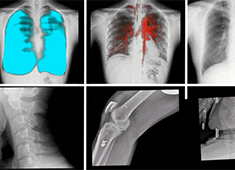

普放類醫療器械有哪些類型 CR/DR/胃腸機DRF介紹

普放類醫療器械,多用于普放科使用,而普放科,可以理解為普通放射科,是在原放射科基礎上分出的新科室,其它部分還有CT室、磁共振室等。普放類醫療器械包括CR/DR/胃腸機DRF這幾種類型。...

拍攝全脊柱X光片 長骨拼接技術和一板成像的區別

出于對全脊柱X光片的拍攝需求,DR長骨拼接和大平板一板成像這兩項技術應運而生。長骨拼接技術是在DR自動控制程序模式下,通過多次連續曝光及圖像采集(6至8次),將多幅有重疊部分的圖像無縫拼接成一幅連貫的整體圖像。...